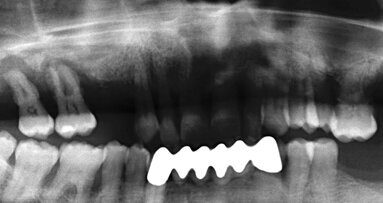

Prvním výkonem v implantologii, kde jsme kostní piezochirurgii použili, je sinus lift. Nejčastější perioperační komplikací při sinus liftu je perforace sliznice čelistní dutiny. V literatuře uváděný výskyt perforace je mezi 14–56 % případů. Řešení vzniklé perforace může být často jednoduché – využitím vstřebatelné membrány či síťky s hemostatikem, někdy je ale až nemožné – hlavně u těžce atrofické sliznice. Piezochirurgie toto riziko významně při správném použití redukuje, a to hlavně v průběhu laterální antrostomie a během počáteční fáze uvolnění membrány. V minulosti byla obtížnější elevace membrány pomocí existujících piezochirurgických elevatorií, neboť k dispozici byly pouze dvě varianty – jedna angulovaná pod úhlem 90 a druhá pod úhlem 120 °. V současné době ale již máme k dispozici elevatoria ergonomická. Přesto není určitě chybou dokončit elevaci membrány manuálními nástroji a specializované koncovky použít pouze v případě přítomnosti anatomické překážky – např. septa v antru (obr. 2).